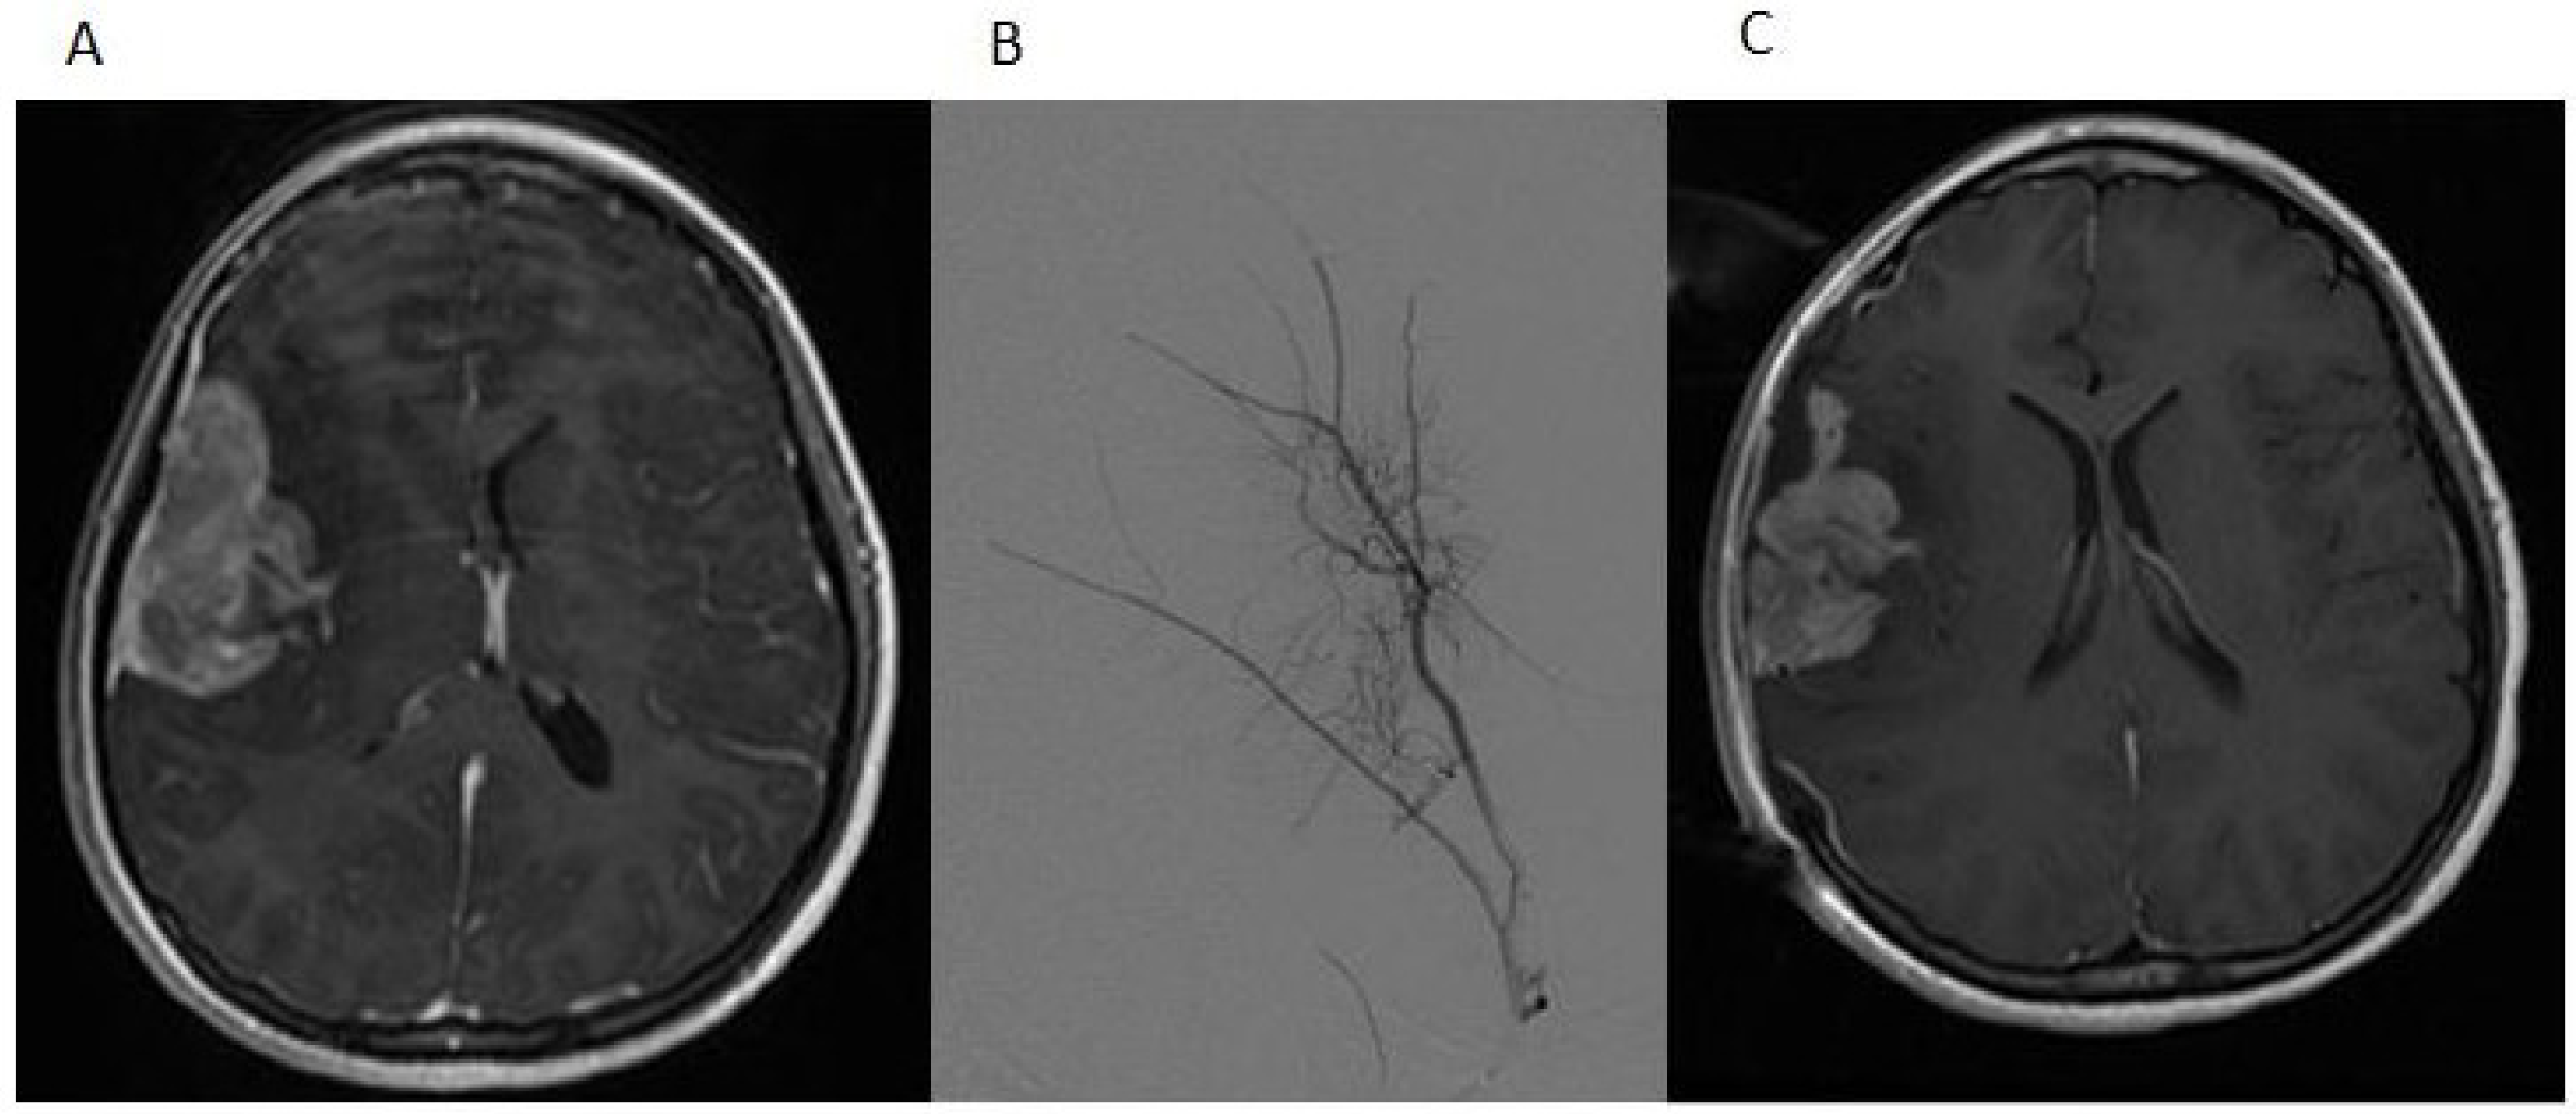

A 12-year-old girl presented with a history of frontal headaches for several weeks after suffering minor head trauma. The initial CT scan without contrast showed no evidence of intracranial bleeding. Because of persistent headaches, however, as well as nausea and vomiting, she underwent another CT scan less than a month later that showed a 6.2 × 3.5 cm right fronto-temporal mass with associated edema and a midline shift. Magnetic resonance imaging (MRI) of the brain with and without intravenous gadolinium was then performed and demonstrated a 5.5 × 2.2 × 5.1 cm, apparently extra-axial mass, largely within the right Sylvian fissure (Figure 1A). The interface of the brain was lobulated and irregular, raising the possibility of the invasion of the brain and subarachnoid space, but no definite intraparenchymal component was recognized. There was vasogenic edema in the subcortical white matter and a 5-mm midline shift towards the left side. Based on imaging, it was felt that the tumor was likely to be a hemangiopericytoma. Physical examination was notable for an intact neurological examination.

The patient underwent a right-sided craniotomy after a successful partial embolization of the tumor the day prior (Figure 1B). A significant portion of the mass was visualized, deep to middle cerebral artery branches shown by intraoperative ultrasound to be coursing through the mass and providing blood supply to the temporal and frontal lobes. The attempted dissection of the tumor off the pial surface also led to devascularization of the underlying brain as the tumor had parasitized the pial vasculature. Therefore, further dissection following superficial excisional biopsy of the mass was not performed for safety reasons. A dural graft was placed. Because of significant brain swelling, the bone flap was not immediately replaced. The temporalis muscle was closed in apposition to the dural graft. Postoperative MR imaging showed that the resection of the anterior and superior aspects of the mass had been accomplished, although the majority of the mass remained (Figure 1C). Microscopic examination revealed a cellular neoplasm with clear or eosinophilic cytoplasm in sheets, small nests and pseudopapillary formations associated with small foci of necrosis (Figure 2A). There were rare mitotic figures. Thin connective tissue bands with blood vessels containing endothelial hyperplasia were frequent. Immunostaining revealed vimentin in all of the tumor cells and scattered tumor cells positive for bcl-2, p53, desmin and factor XIIIa. CD99 and CD34 were negative. The mitotic labeling index using Ki-67 staining was approximately 10%. The initial pathologic diagnosis was hemangiopericytoma.

Figure 1. (A) The post-contrast T1-weighted MRI image shows a predominantly heterogeneously enhancing mass extending into the right Sylvian fissure with probable invasion of the adjacent insular cortex; (B) a select image from the tumor embolization demonstrates a dramatically hypervascular tumor supplied by branches of the right middle meningeal artery that was successfully embolized with polyvinyl alcohol particles; (C) the postoperative T1-weighted MRI image with contrast demonstrates partial resection of the tumor.